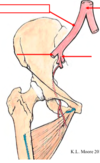

Identifiez